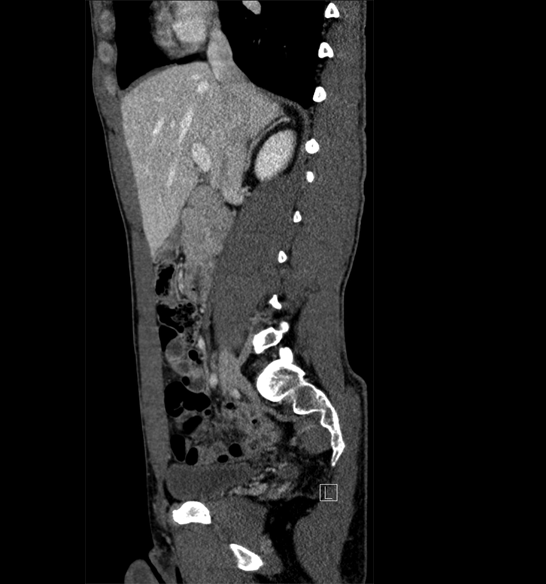

Body

Covers abdominal CT anatomy.